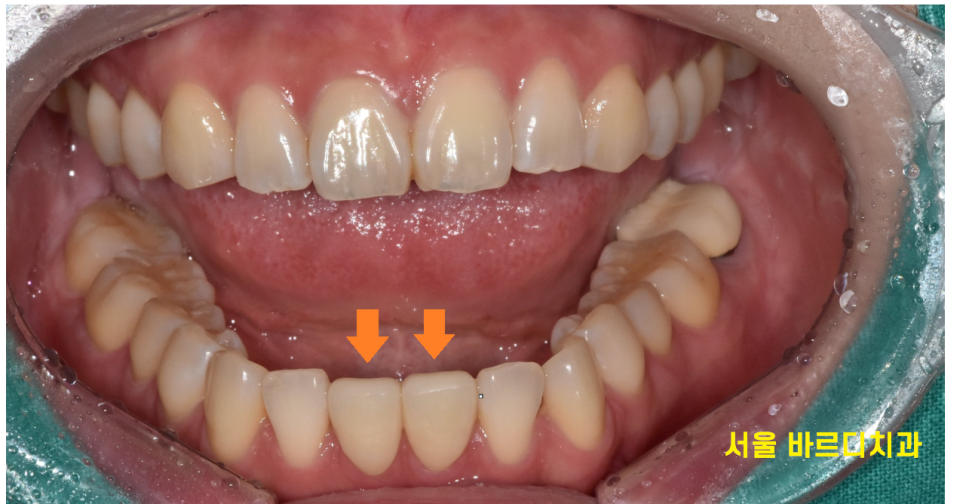

231116

벌어진 아래 앞니 공간이 싹 메꿔졌죠?

3군데 정도 공간이 있었는데

감쪽같게 메꿔드렸습니다.

단 2개 앞니 라미네이트 치료를 했을 뿐인데

공간이 메꿔지면서 이미지도 세련되게 변신하셨어요.